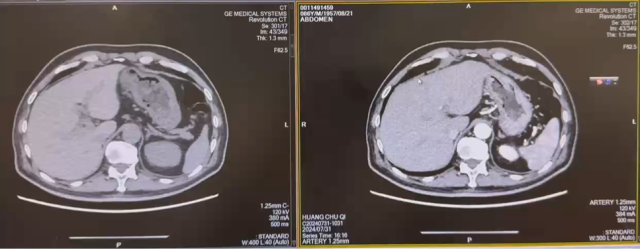

影像学检查

2023-05-03:

2023-08-01: